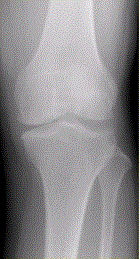

问题 患者女,54岁,右膝关节痛。实验室检查:类风湿因子阳性,除外膝关节类风湿性关节炎。X线检查结果如下图。 判断类风湿性关节炎活动性的检查方法是

选项 A.CR B.CT C.MRI D.MRI增强检查 E.动态增强MRI

答案 E